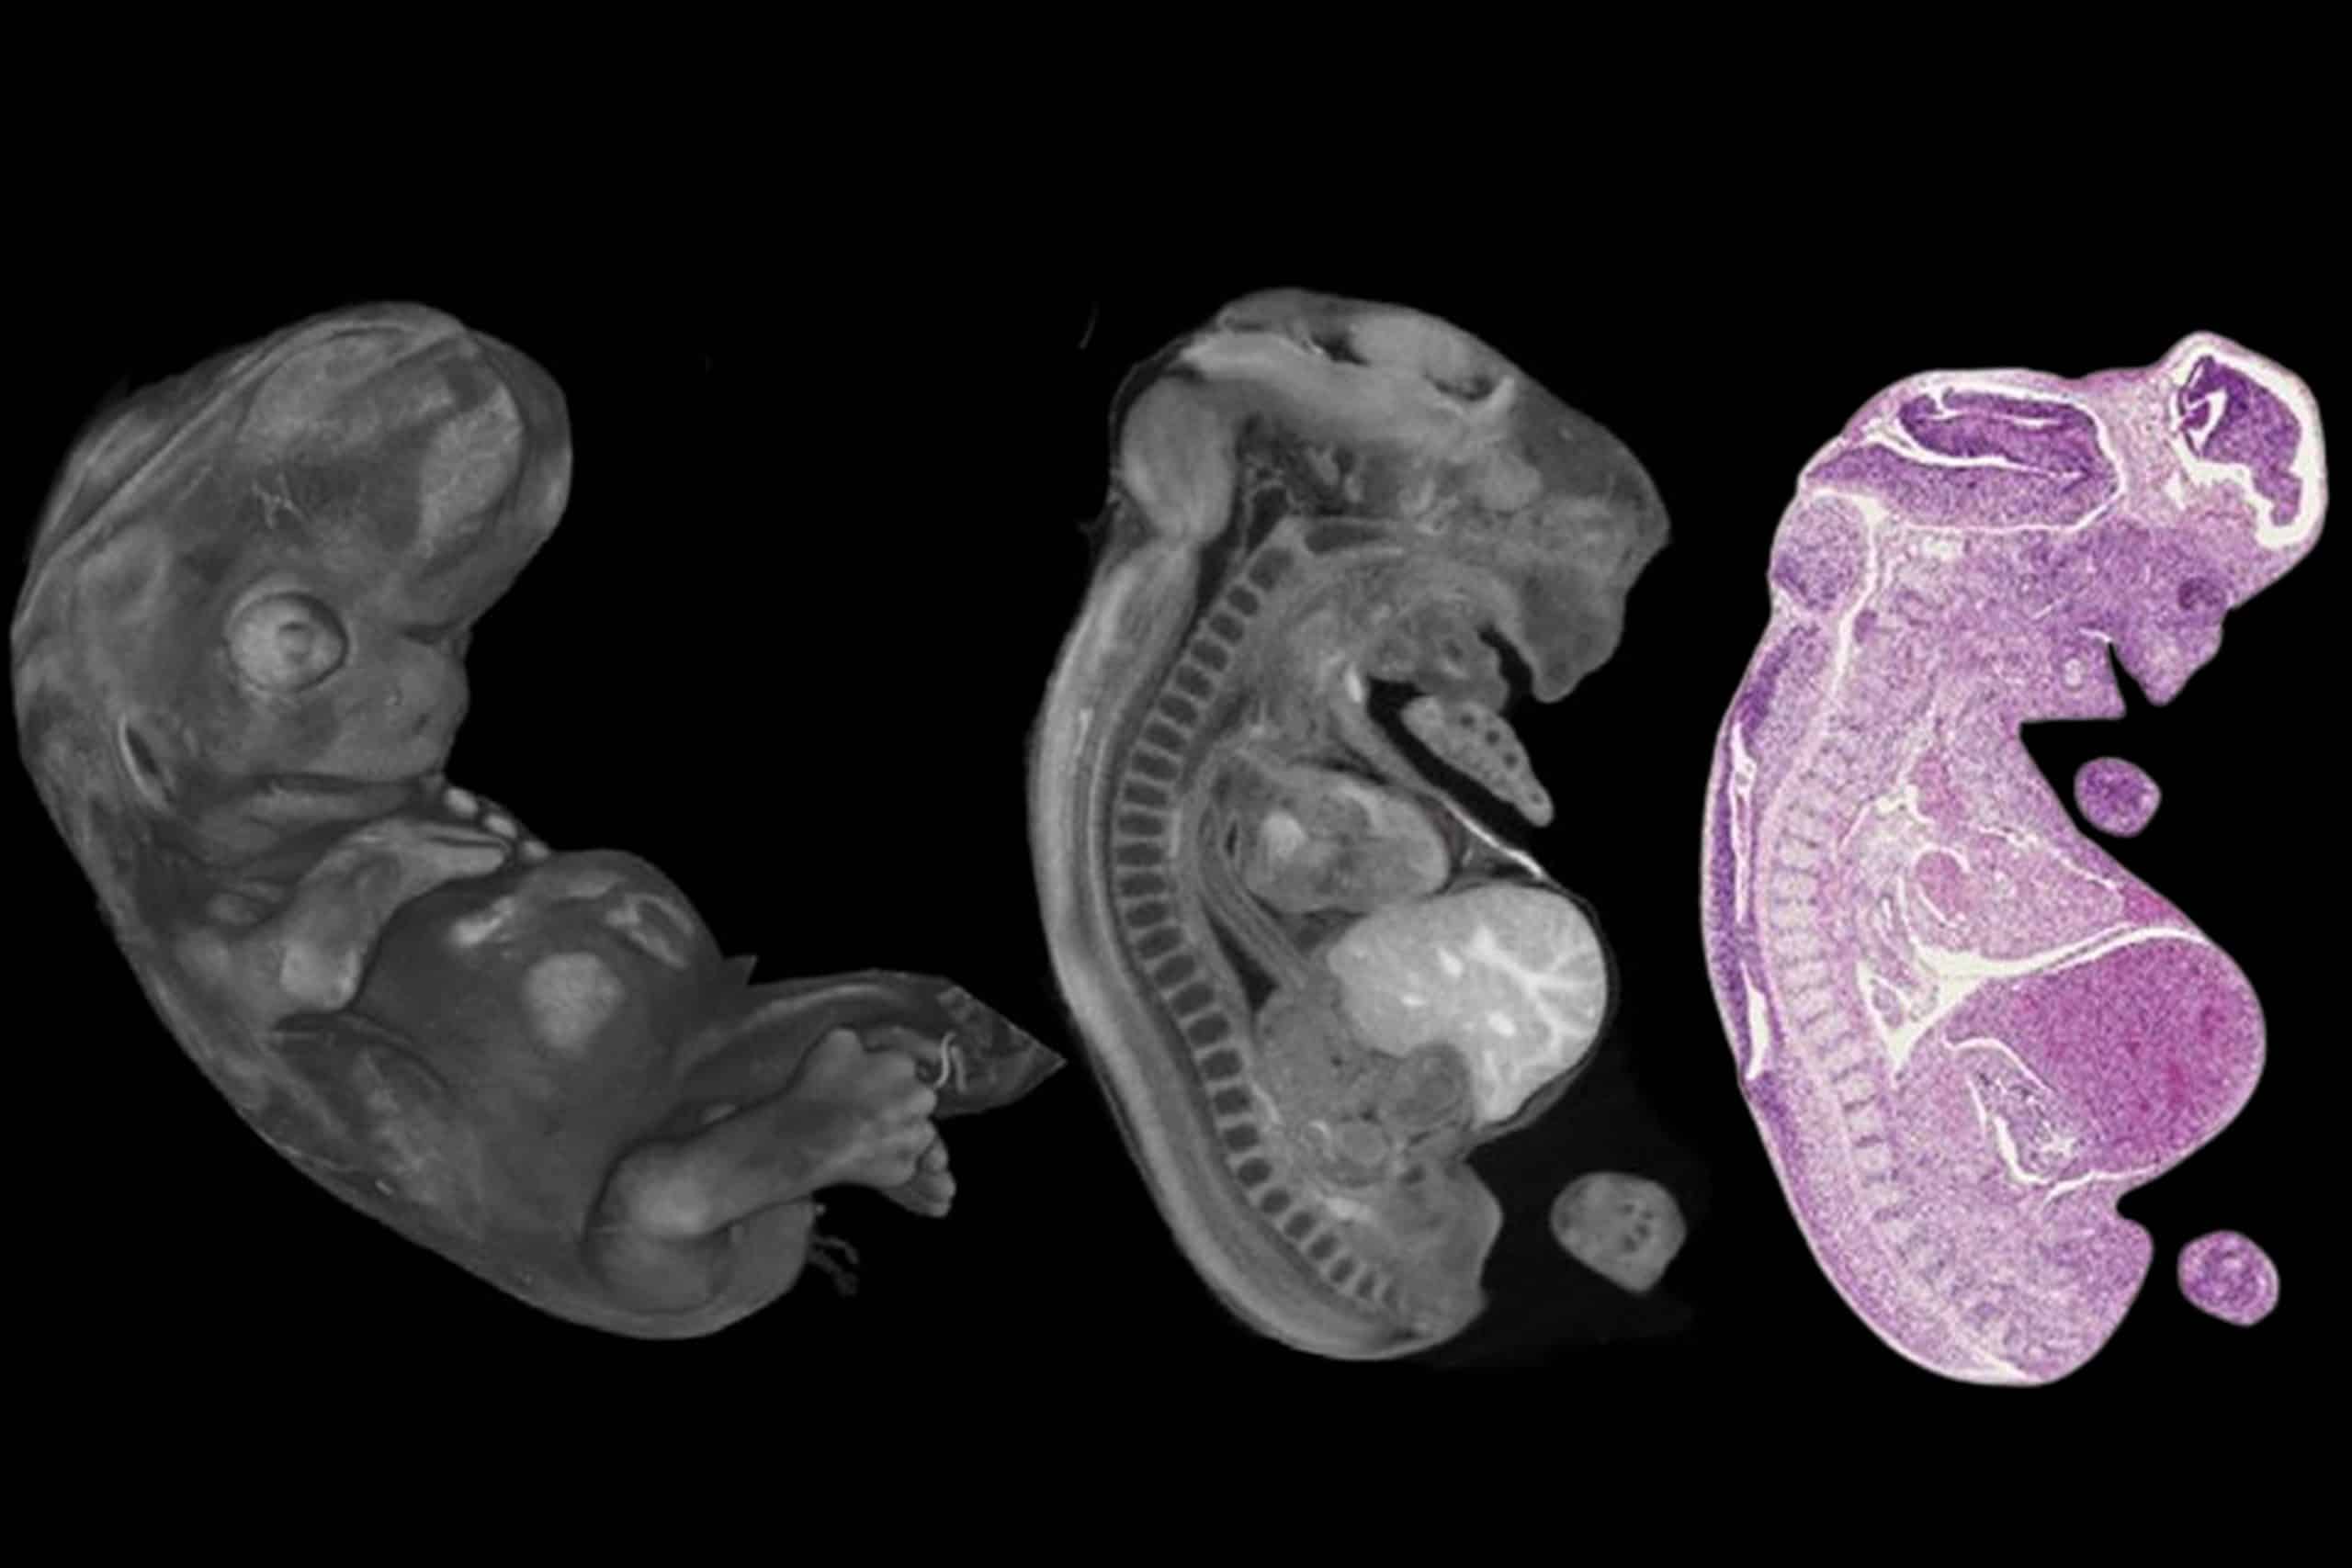

A Semmelweis Egyetemen szerzett eddigi tapasztalatokat dr. Maurovich Horvat Pál, az OKK igazgatója és dr. Dudás Ibolyka, az OKK Radiológiai Tanszékének klinikai főorvosa ismertette, míg dr. Beke Artúr, a Szülészeti és Nőgyógyászati Klinika egyetemi docense a magzati diagnosztika genetikai vonatkozásairól beszélt. Dr. Molnár Béla, a Belgyógyászati és Onkológiai Klinika kutatóprofesszora, a 3DHISTECH startup alapítója és tulajdonosa arról számolt be, hogy régi álma, a háromdimenziós digitális szöveti szintű képalkotás valósult meg a cég legújabb fejlesztésével, a mikro CT scannerrel. A mikro CT-s képalkotás kiválóan alkalmazható a posztmortális magzati diagnosztikában, ahogyan ezt dr. Száraz Lili PhD-hallgató és Arthurs professzor bemutatták.

A noninvazív posztmortem vizsgálati technikák lehetőséget teremtenek arra, hogy a boncolást kegyeleti okból a lehető legkisebb invazivitással végezzük el, különböző képalkotó eljárások alkalmazásával, amelyek között lehet MRI, CT, microCT vagy posztmortem ultrahang – mutatott rá dr. Marton Tamás. Ezeknek a módszereknek a segítségével lehet azonosítani a magzati anatómiát és a fejlődési rendellenességeket, elsősorban a központi idegrendszer vonatkozásában, illetve célzott szövettani mintavételt is lehetővé tesznek minimálisan invazív módon. Az eljárás multidiszciplináris megközelítést igényel a radiológus, patológus és a magzati medicina szakembereinek részéről. A non-invazív és minimálisan invazív boncolás olyan előremutató irányzat, mely átveheti a hagyományos boncolás helyét – tette hozzá.